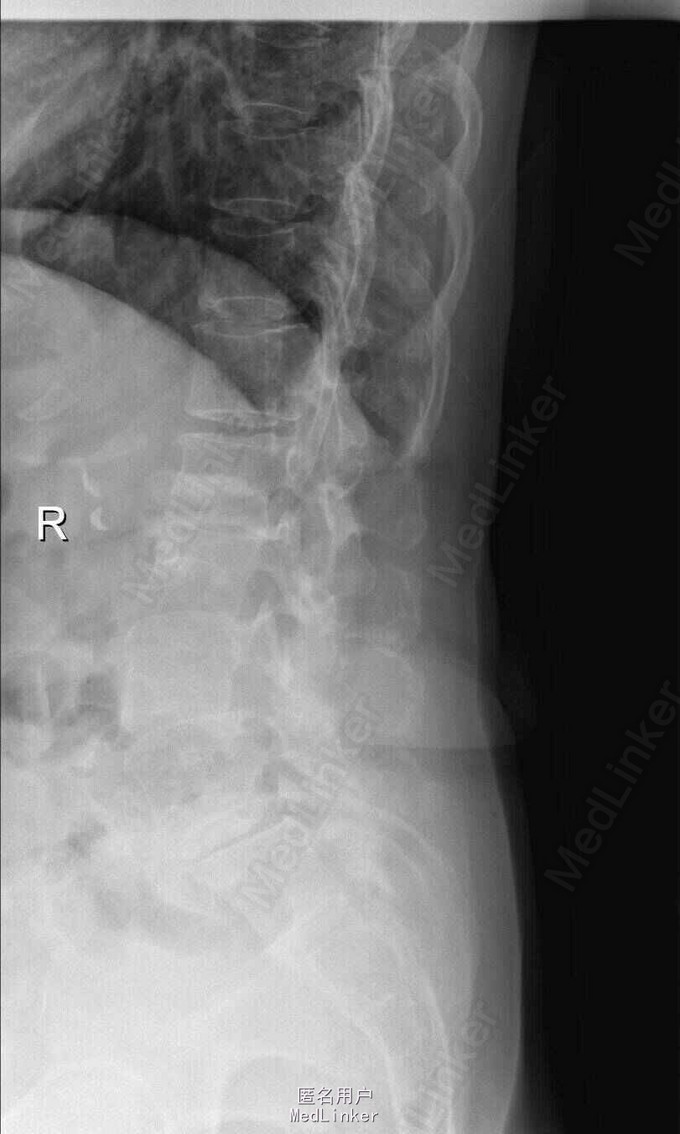

主诉:右下肢麻木伴驼背11年余 病史:患者女性,64岁,11年前无明显诱因出现右下肢疼痛,休息后好转。未予重视,后出现右下肢麻木感,逐渐小狐仙右臀部坚硬,驼背,伴跛行。常感双腿酸胀,腰部疼痛。自行步行距离小于200米,即会发生右下肢僵硬,麻木疼痛。X线检查示腰椎侧弯

查体:脊柱侧弯,上肢无麻木,疼痛感觉异常,腰部右侧疼痛,右下肢及右臀部疼痛,麻木感。双侧肌力及肌张力可,膝腱反射(+),踝反射(+),病理征(—),直腿抬高试验。右侧40度,左侧55度。 辅助检查:腰椎x线片:腰椎侧弯,腰椎退行性改变,L5椎体略行前滑脱 脊柱全长:胸腰段呈S形,L5椎体向前滑脱,L3椎体略变扁,颈胸腰椎退行性改变 MRI:脊柱侧弯,L2-3,L3-L4,L4-L5,L5-S1椎间盘突出,相应节段椎管狭窄